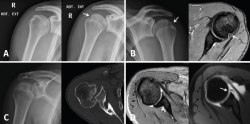

Small Hill-Sachs lesions (HSLs) in AP projection are only visualized with the shoulder in internal rotation (Figure 5A and B), while larger lesions can be seen in both internal rotation and external rotation(20) - the axillary projection affording better visualization of HSLs, however. For assessing glenoid bone loss, it is advisable to use an axillary projection or modified Bernageau projection, with a sensitivity and specificity of over 90%(20,21).

Figure 5. A and B: two cases of patients with Hill-Sachs lesions. A: comparison showing that it is easier to visualize the defect with the shoulder in internal rotation, especially in the case of a small defect; B: the same Hill Sachs lesion is observed on a comparative basis in the plain radiograph and MRI scan; C: computed axial tomography (CAT) view of a reverse Hill-Sachs lesion; D: ALPSA type lesion in conventional magnetic resonance imaging (MRI) and arthro-MRI. The latter technique is useful in the event of diagnostic doubt, since it offers more precise information about the type and characteristics of the capsulolabral lesion.

If these bone lesions are visible on plain radiographs, they can be assumed to be of considerable size; a CAT study therefore would be indicated to quantify the defect.

Three-dimensional reconstructions afford valuable information about the morphology of the glenoid cavity, as well as precise measurement of the size, location and depth of the defects of the humeral head (Figure 5C) and glenoid cavity(19,22) - these being decisive factors for the planning of surgery.